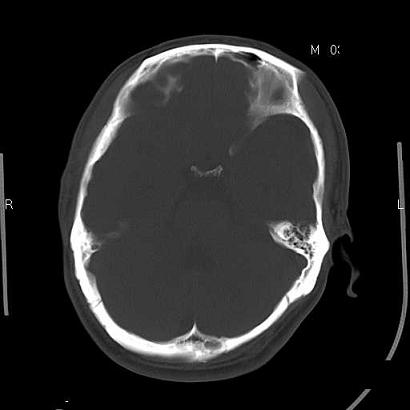

男,39岁,外伤来诊,老师们看看枕骨是什么病

蛛网膜颗粒压迹特点:位于中线两侧的颅骨圆形或类圆形低密度影,常多发,可融合,边缘有硬化缘,无软组织肿块。

枕内隆突左缘板障区示不规则囊状透亮区,颅骨内外板规整,无膨胀及缺损,周围无软组织肿块,考虑板障血管性病变,1.板障静脉湖,2.枕骨血管瘤(局部无膨胀性改变,无硬化环及钙斑影,故不太支持)。

蛛网膜颗粒压迹不会象这样有清晰的内板显示的!压迹压迹肯定是把内板压到板障里撒!各位老师同意不?